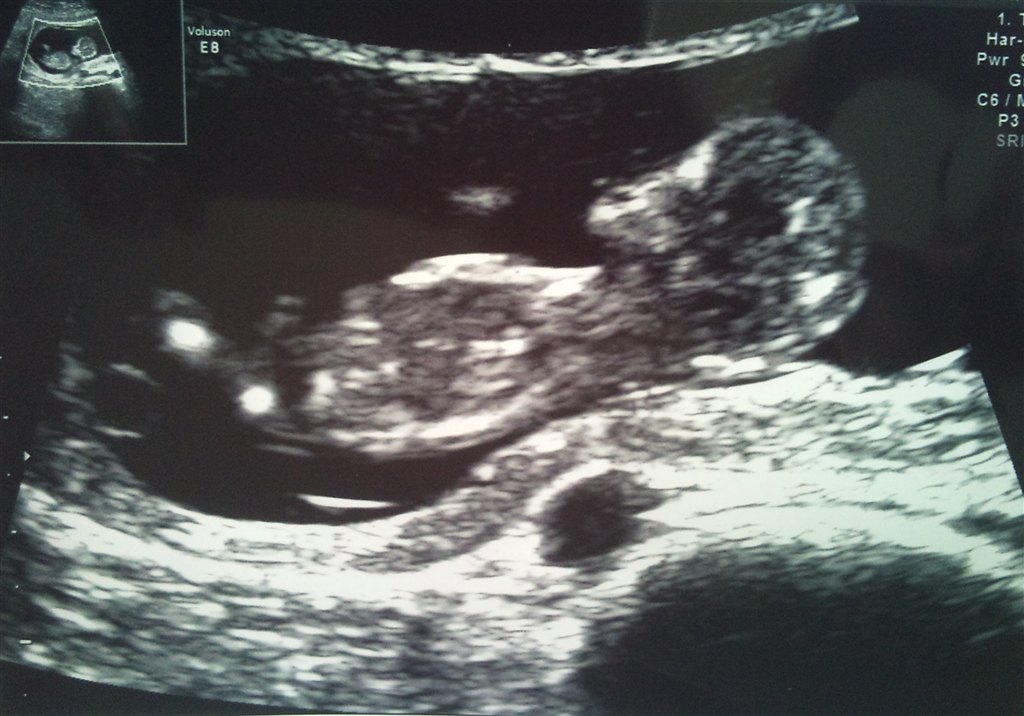

Jeg har en lille livlig krabat i maven, som slet ikke ville ligge stille i starten + det lignede den havde hikke! Den blev dog mere rolig og vi kunne se hjerte (inkl. 4 hjertekamre), blære, mavesæk, hjerne, arme, ben osv. og alt så normalt ud og som det skulle. Det var bare så stort, at se den lille for første gang

Risikotal 1:3640, så det er jo som det skal være.

Og så et lille billede også